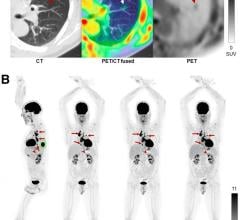

Positron emission tomography (PET) is a nuclear imaging technology (also referred to as molecular imaging) that enables visualization of metabolic processes in the body. The basics of PET imaging is that the technique detects pairs of gamma rays emitted indirectly by a positron-emitting radionuclide (also called radiopharmaceuticals, radionuclides or radiotracer). The tracer is injected into a vein on a biologically active molecule, usually a sugar that is used for cellular energy. PET systems have sensitive detector panels to capture gamma ray emissions from inside the body and use software to plot to triangulate the source of the emissions, creating 3-D computed tomography images of the tracer concentrations within the body.

Precision can have an enormous impact on patients. From diagnosis to patient monitoring (see “How Digital PET/CT Can ...